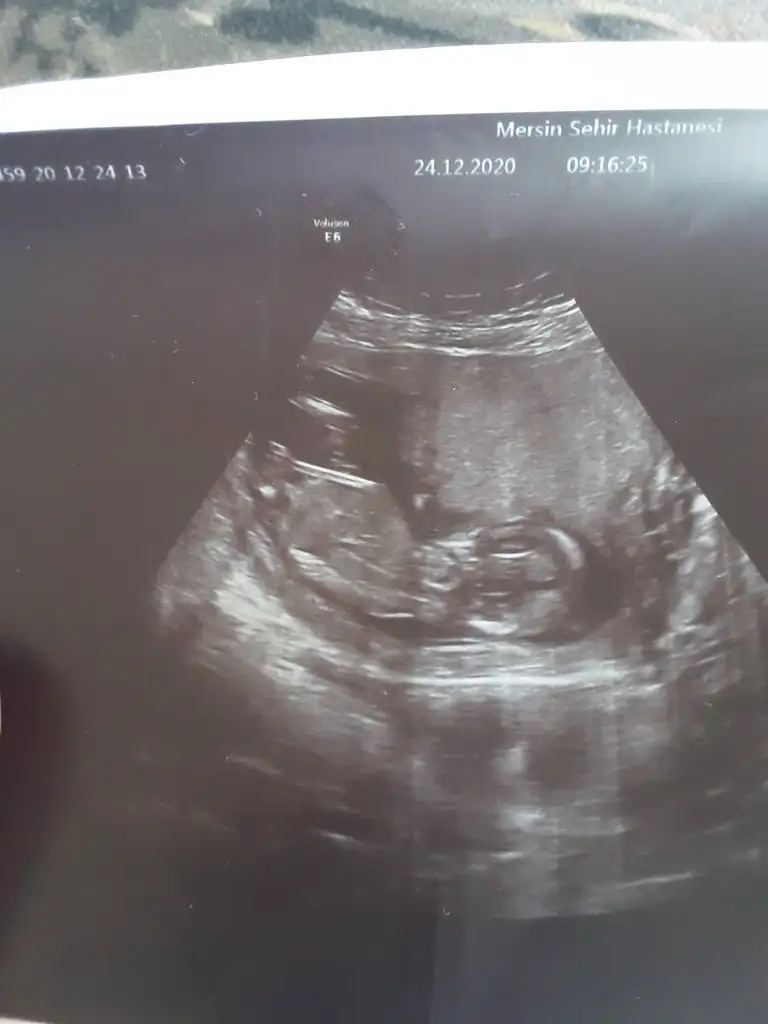

Benim için de tahmin yürütür müsünüz?

Eklentiler

• IMG_20210220_141757.webp

IMG_20210220_141757.webp

20,4 KB · Görüntüleme: 159